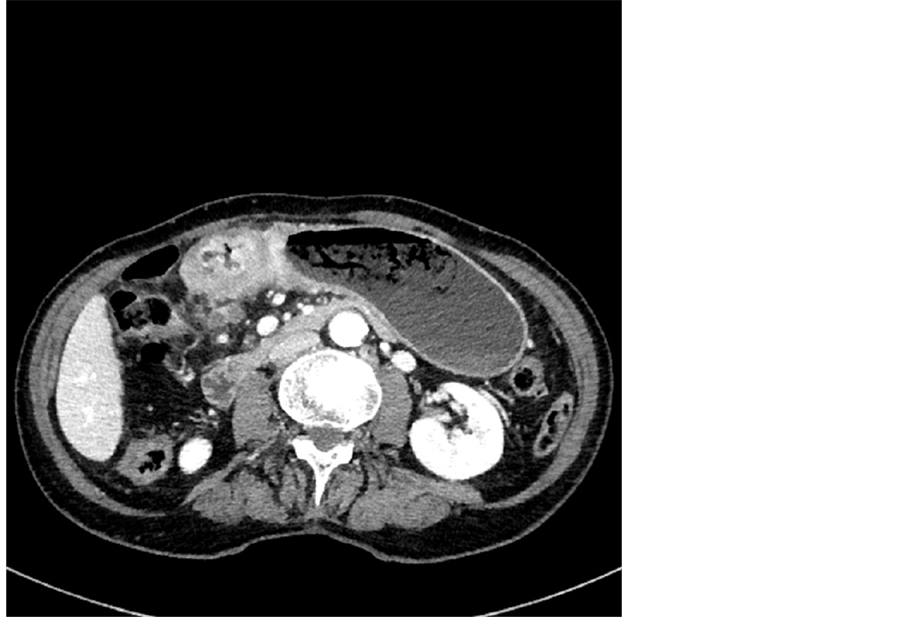

Figure 2. MDCT image in axial plane-T4b tumor with peritoneal involvement.

Three patients were correctly staged as T4b: they showed marked wall thickening (22 - 28 mm), with extensive stenosis of the lumen. The gastric wall showed a two-layer aspect, in presence of an irregular appearance of the outer margin and perigastric fat, with infiltration of adjacent organs.

Among the 15 patients included in the study, 3 showed ascites and nodular lesions on peritoneal surface: in all three cases, cytological examination of peritoneal fluid and histologic analysis on peritoneal nodules obtained during surgery confirmed the presence of peritoneal carcinomatosis.

Quantification of peritoneal involvement evaluated with Sugarbaker’s PCI showed scores between 4 and 26. Loculated ascites was present in all three cases.